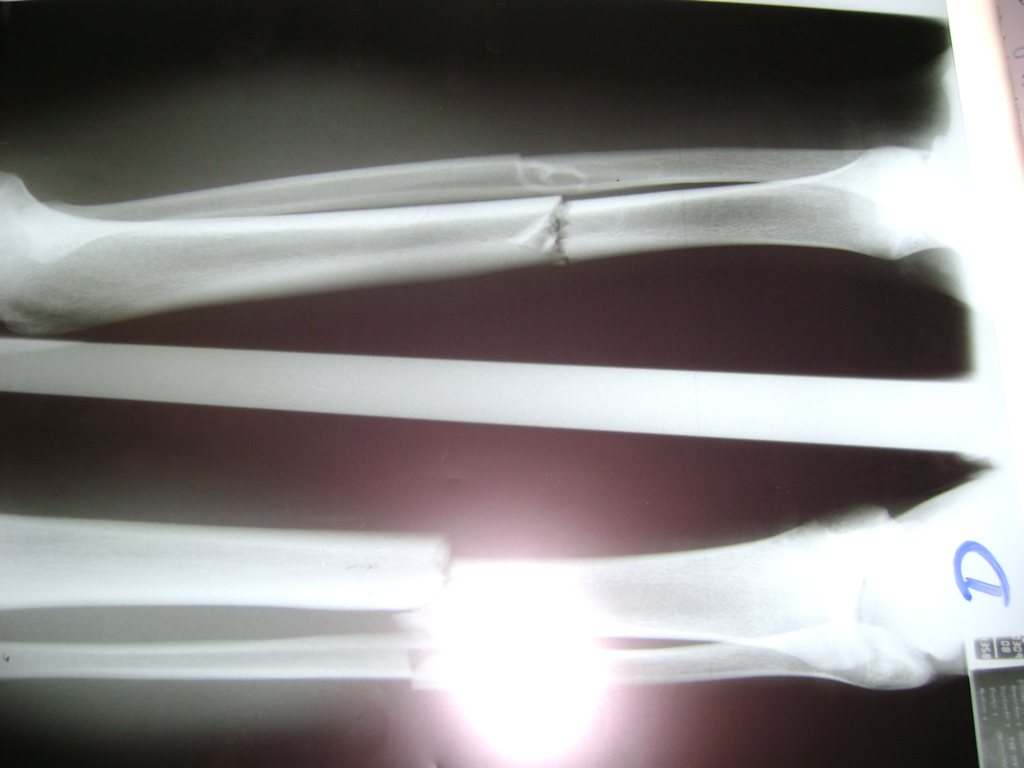

Aunque cada uno de estos huesos puede fracturarse por separado, normalmente la rotura es una lesión que se produce de forma conjunta

La mayor parte de las roturas implican a la parte proximal del hueso (parte del hueso próximo a la rodilla) o a la parte distal (parte del hueso cerca del tobillo).